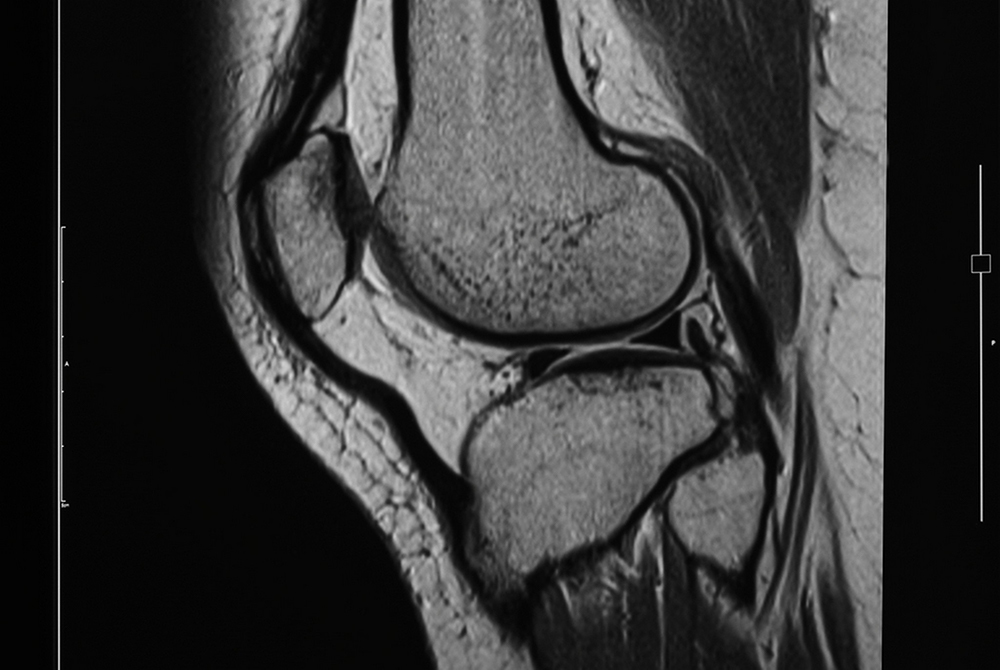

Magneettikuvaus on käyttökelpoinen tapa kuvata koko kehoa. Se sopii niin tuki- ja liikuntaelimistön kuin pään alueen tutkimukseen. Osa metalleista on ferromagneettista ainetta. Ferromagneettiset kappaleet kehossa ovat kuvauseste, koska ne vuorovaikuttavat voimakkaasti magneettikenttien kanssa. Kuvattavalla voi olla metalliproteesi, mutta sydämentahdistin saattaa olla kuvauseste. Ensimmäiset magneettikuvauslaitteet tulivat Suomeen 1980-luvulla. Nykyään laitteita on lukuisissa sairaaloissa ja niitä on kulkenut Suomessa rekan perävaunuissa jo vuodesta 1996 lähtien. Alla on magneettikuva ihmisen polvesta.